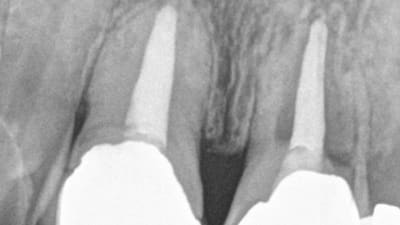

Maintenance Successful Collaborative Management of Peri-Implantitis with a Regenerative Approach Stuart J. Froum, DDS October 01, 2012

Maintenance Partnering to Manage Hard- and Soft-Tissue Peri-Implant Complications in the Esthetic Zone Donald S. Clem, DDS, George R. Perri, DDS October 01, 2012